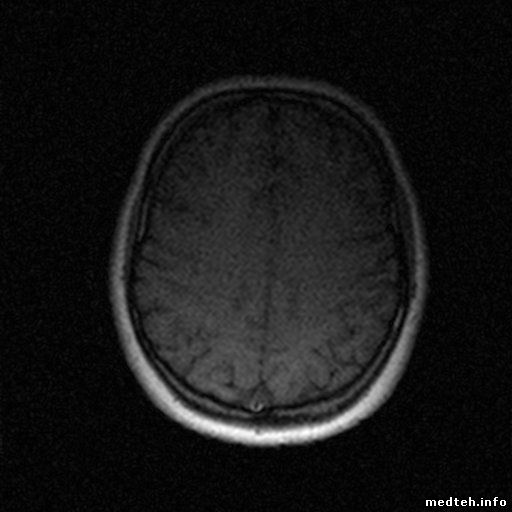

Доброго времени всем, помогите пожалуйста разобраться с чудом китайского мед. прома. Аппарат перестал выдавать читаемую картинку, пропала детализация и контраст +картинка стала шумновата, подскажите в какую сторону смотреть? Мануалов нет, из того что знаю по нему подстраивал offs на градиентах (на картинку не влияет).

7558872.jpg (38.7 Kb) · 5127933.jpg (31.7 Kb)